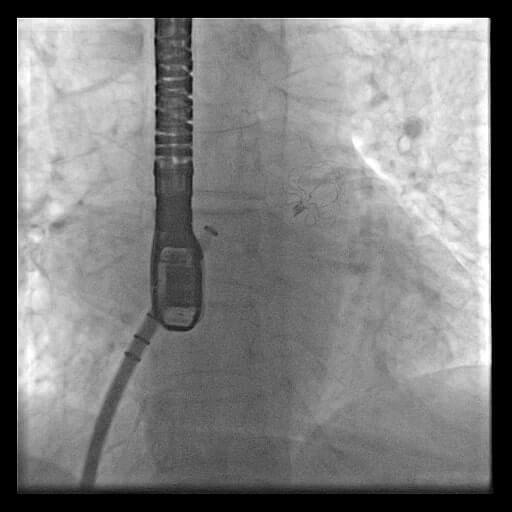

Left atrial appendage device closure with WATCHMAN device for atrial fibrillation

She had a CHA2DS2-VASc score of 4. Therefore, she needed anticoagulation, but she was at high bleeding risk. The WATCHMAN device implantation was done to reduce stroke risk and avoid bleeding complications due to anticoagulation. This is the first-ever procedure done in both Telugu-speaking states.